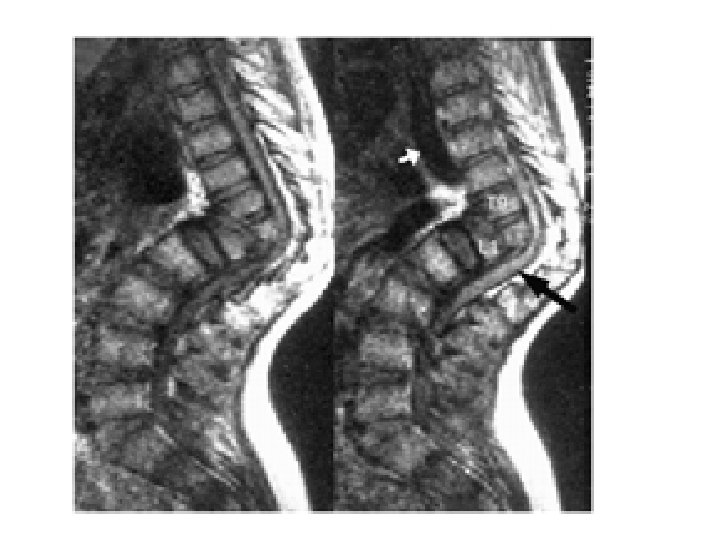

Tuberculosis of the Spine- Pott’s Disease • As a form of extrapulmonary tuberculosis that impacts the spine, Pott’s disease has an effect that is sometimes described as being a sort of arthritis for the vertebrae that make up the spinal column. More properly known as tuberculosis spondylitis, Pott’s disease is named after Dr. Percivall Pott, an eighteenth century surgeon who was considered an authority in issues related to the back and spine. Pott's disease is often experienced as a local phenomenon that begins in the thoracic section of the spinal column. Early signs of the presence of Pott’s disease generally begin with back pain that may seem to be due to simple muscle strain. However, in short order, the symptoms will begin to multiply.

Kyphosis • With kyphosis, your spine may look normal or you may develop a hump. Kyphosis can occur as a result of developmental problems; degenerative diseases, such as arthritis of the spine; osteoporosis with compression fractures of the vertebrae; or trauma to the spine. It can affect children, adolescents and adults.

Scoliosis • Scoliosis is an abnormal curvature of the spine. If your child has scoliosis, the view from behind may reveal one or more abnormal curves. Scoliosis runs in families, but doctors often don't know the cause. More girls than boys have severe scoliosis. Adult scoliosis may be a worsening of a condition that began in childhood, but wasn't diagnosed or treated. In other cases, scoliosis may result from a degenerative joint condition in the spine.

The Vertebral Column · Vertebrae separated by intervertebral discs made of cartilage · The spine has a normal S curvature · Each vertebrae is given a name according to its location Copyright © 2003 Pearson Education, Inc. publishing as Benjamin Cummings Figure 5. 14 Slide 5. 28